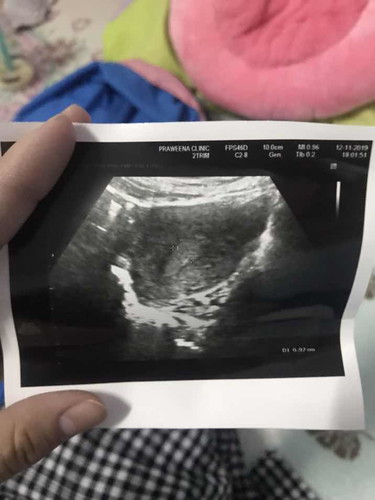

ท้องไม่ถึงเดือนค่ะ แล้วมีเพศสัมพันธ์กับแฟน ตื่นมาตอนเช้า มีเลือดไหลออก มา ไม่เยอะค่ะ 2 หยดได้ ไม่ได้เอะใจ แต่พอ ตอนบ่าย ก็ไหลอีก ไม่เยอะมาก แต่ก็กลัวเลยรีบไปหาหมอ กลัวน้องจะหลุด พอไปหมอก็ซาวให้ดู บอกว่าน้องยังอยู่ แต่อายุครรภ์ยังไม่ถึงเดือน และได้ฉีดยากันแท้งให้ พร้อมกับให้วิตามินมาทาน แล้วบอกให้ไปตรวจอีกทีหลัง 2 อาทิตย์แต่พอกลับมาแล้ว เลือดยังไหล กระปริบกระปรอย เหตุเกิดตั้งแต่ วันที่12 พฤศจิกายน ค่ะ วันนี้วันที่ 17 แล้ว ยังมีคราบเลือดจางๆ ติดกางเกงในนิดหน่อย อยากทราบว่าเป็นอันตรายไหมคะ ต้องทำยังไงต่อ หรือรอให้หายไปเอง แล้วค่อยรอไปตรวจอีกที ขอคำแนะนำหน่อยค่ะ ตอนนี้กังวลกลัวไปหมด เป็นท้องแรกค่ะ